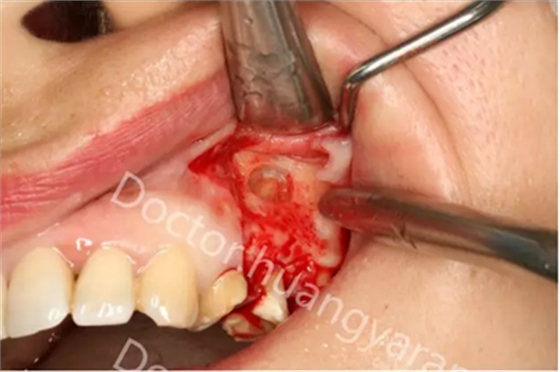

拍攝根尖片檢查,24、25牙根充到位,但考慮到可能是治療過程中消毒不到位導致,所以重新對25牙做根管治療,但酸痛感無減輕,于是考慮到根尖骨穿孔的可能性,與患者溝通后做診斷性翻瓣,翻瓣后發(fā)現(xiàn)根尖處無頰側(cè)骨板直接暴露,當即行根尖切除術(shù),對位縫合,經(jīng)兩個月恢復根尖已無酸痛感!